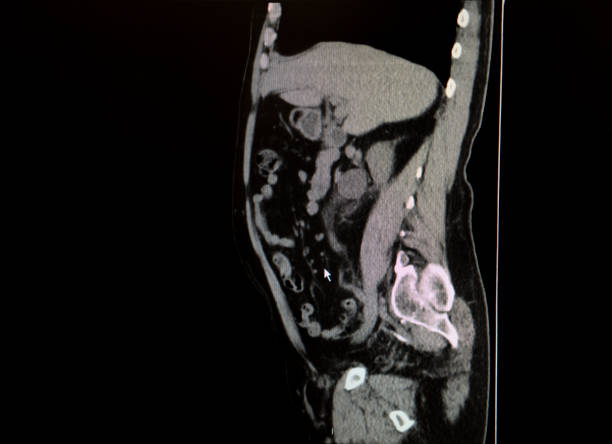

추간판 탈출증은 경추 사이의 쿠션 역할을 하는 추간판(탈장)이 밀려나와 주변 신경근을 압박하여 통증을 유발하는 질환인데 이를 목디스크라고 합니다. 높은 베개를 베고 자다가 목에 긴장을 당했을 때나 교통사고로 등으로 발생합니다. 하지만 가장 목디스크에 가장 큰 이유는 습관적인 나쁜 자세로 장기간 지속되는 나쁜 자세는 퇴행성 변화를 동반하며 40세 이후 중년층에서 목디스크는 더 흔하게 나타납니다.

탈출된 디스크로 인한 통증은 탈출된 디스크가 찢어지고 척수 신경을 압박하여 상처에 염증을 일으킬 때 발생합니다. 증상은 손실된 디스크의 위치나 신경에 가해지는 압력에 따라 다른데 가장 흔하게 나타나는 증상은 인후통으로 목 뒤에서 어깨나 팔까지 통증을 유발하여 손의 감각 이상으로 이어질 수 있습니다. 이 증상에 주의를 기울이지 않으면 손가락의 감각이 둔해지고 주먹을 쥐는 힘이 약해질 정도로 심해집니다. 실수로 물 한 컵을 바닥에 떨어뜨린 적이 있다면 경추 추간판 탈출증을 의심해야 합니다. 마비된 목의 기저부에 있는 4쌍의 신경근이 경추에서 나와 어깨, 팔, 손가락에 닿기 때문에 따라서 목디스크에 좋은 운동을 미리미리 하는 것이 좋습니다.